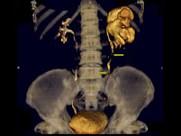

问题 男,58岁,尿频,尿痛伴低热乏力2月,CT如图所示,下列说法正确的是 ( )

选项 A.左侧肾盂肾盏扩张,其边缘不整 B.左侧输尿管多发性狭窄 C.左侧肾结核 D.左侧输尿管结核 E.左侧输尿管癌

答案 ABCD